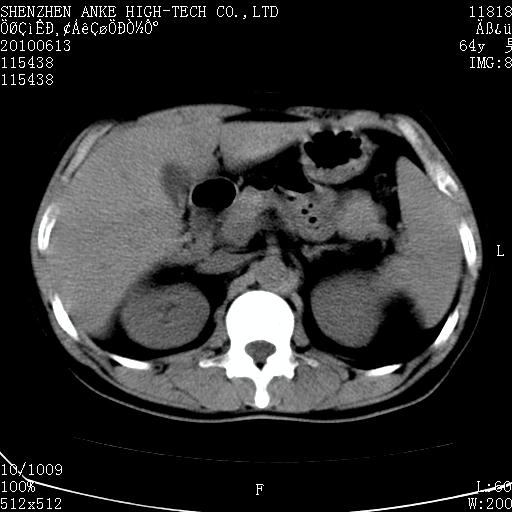

以下是引用beifangren在2010-7-26 22:05:00的发言:[br]左肾中极圆形占位,肾盏肾盂受压移位,建议增强。结合肺部结节。肝低密度灶,多为肾癌并肺部、肝转移。